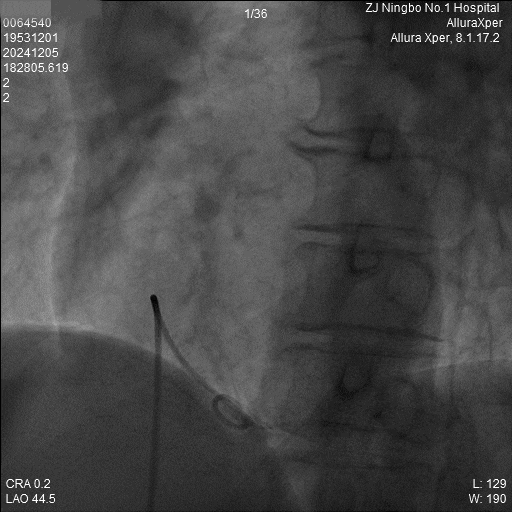

1.猪尾导管造影:软钢丝配合猪尾导管进入RV,造影显示RV轮廓。

b) LAO 45